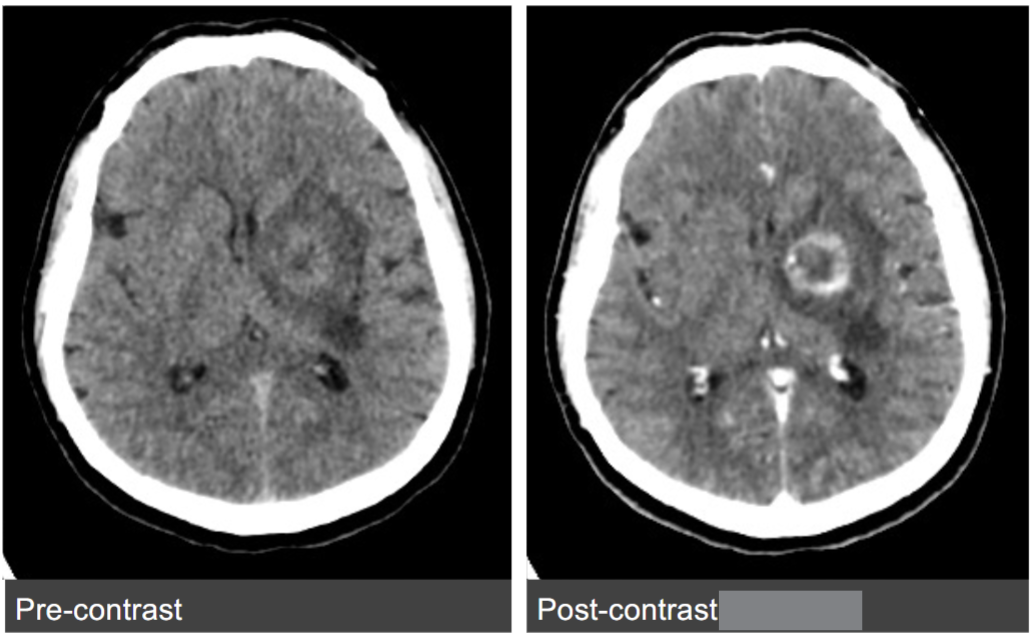

Contrast scanning protocol of brain

50mL ICM IV, 1mL/sec

5min delay before scan

Name the pathology

Glioma